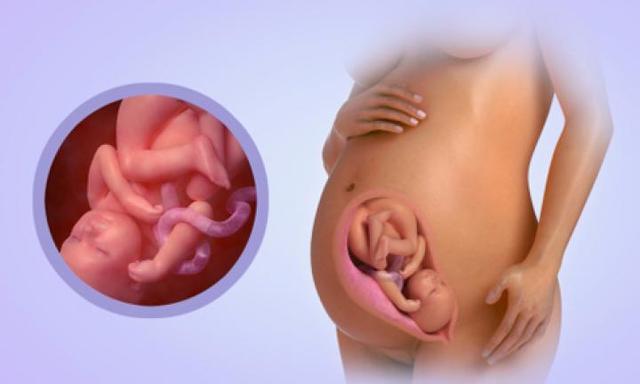

• Week Twenty-Six: End of Second Trimester

Week Twenty-Six: End of Second Trimester

The baby is very active in the womb and did you know that thumb sucking calms your child and tightens the jaw? So dont yell at kids that arent your kids to stop sucking their thumbs. Their brain is still developing and he can open his eyes now!

• Week Twenty-Seven

Week Twenty-Seven

Since the brain is still developing, remember to talk or read to your peanut and keep bumpin' new Zayn album. If you shine a light into your belly, why would you do that, but if you do, your baby will turn it's head since he can open his eyes as his reina develops.